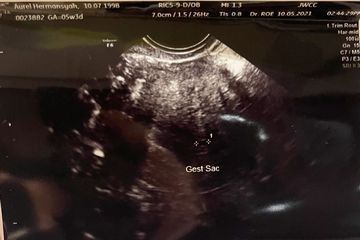

Hasil USG Aurel Hermansyah saat keguguran (sonora.id)